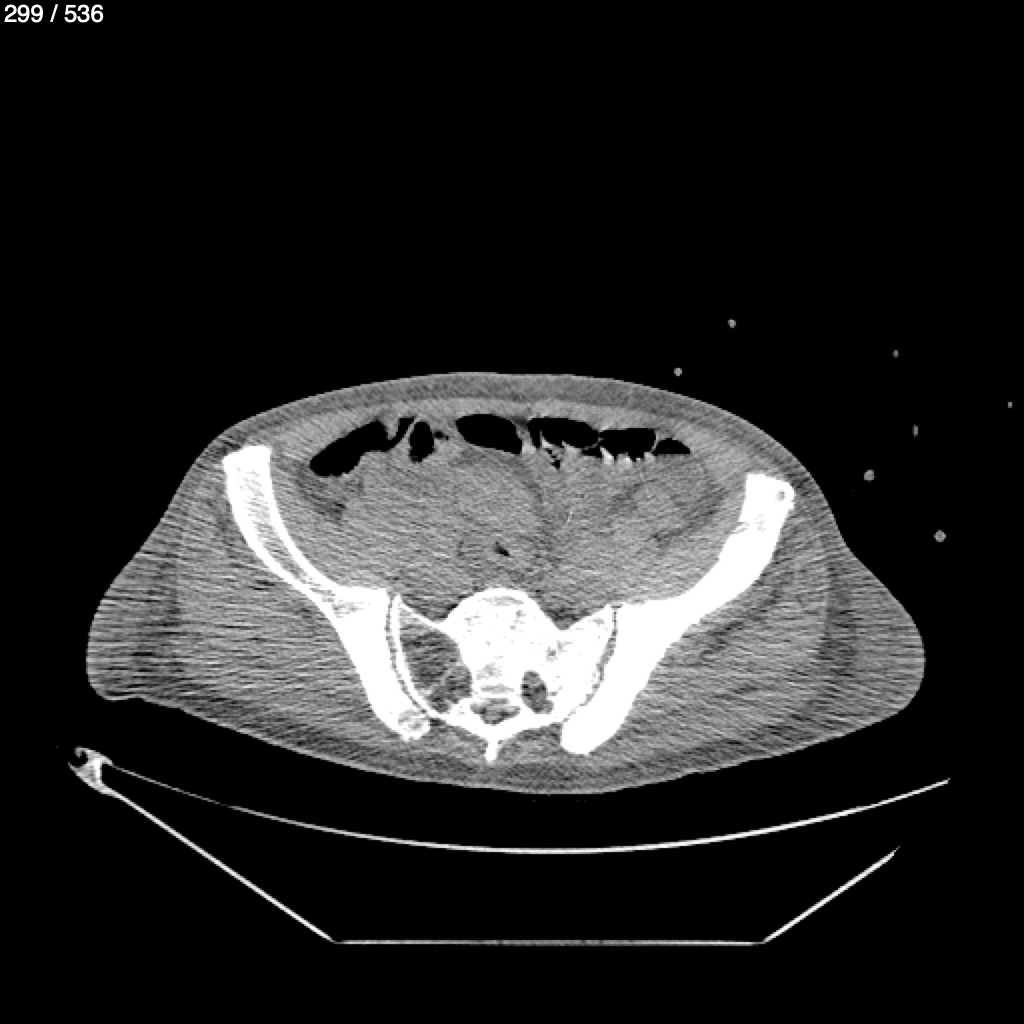

Angel Villalobos Palomeque 73 A - T.C Abdomen Simple